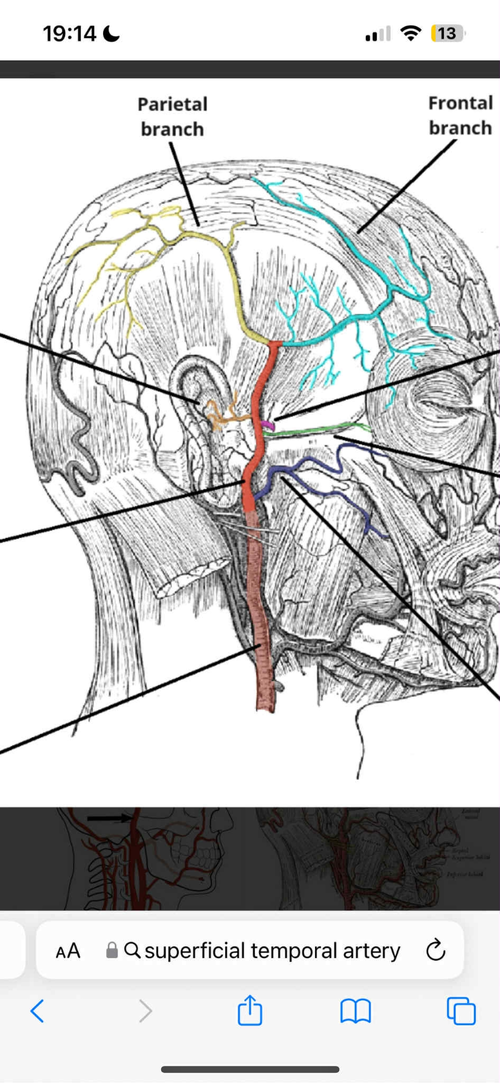

One other explanation as to why people that are recessed in the mandible area or have had extraction-retraction and been forced to be recessed through decreased ap space are the superficial temporary artery(see image 3).

The superficial temporary artery are the main bloodprovider to the hair follicles. When your mandible are too far back either by just having a recessed mandible or the mandible are trapped because of lack of ap space the superficial temporary artery can’t provide enough blood to the hair follicles, they basically die and you lose hair.

One other explanation as to why people that are recessed in the mandible area or have had extraction-retraction and been forced to be recessed through decreased ap space are the superficial temporary artery(see image 3).

The superficial temporary artery are the main bloodprovider to the hair follicles. When your mandible are too far back either by just having a recessed mandible or the mandible are trapped because of lack of ap space the superficial temporary artery can’t provide enough blood to the hair follicles, they basically die and you lose hair.